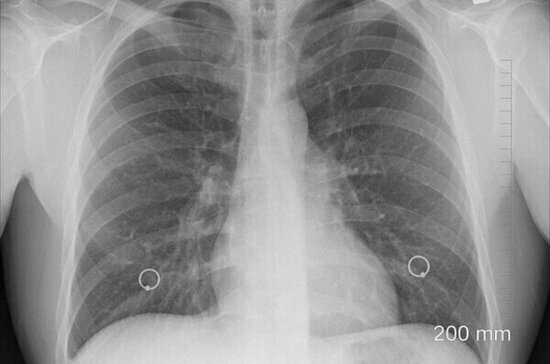

В 90 процентах случаев курение становится причиной рака лёгких. В остальных ситуациях к заболеванию приводит ряд факторов, рассказал в эфире программы «О самом главном» на телеканале «Россия 1» врач и телеведущий Александр Мясников.

«Уж больно агрессивная болезнь. Как не верти, это причина номер один смерти от онкологии. Два миллиона людей в год умирает от рака лёгкого. Почти в 90 процентах случаев курение — причина рака лёгкого», — цитирует доктора «Царьград».

При этом эксперт отметил, что рак лёгких бывает разным. Мелкоклеточный рак встречается только у курильщиков, а вот аденокарцинома не всегда связана с курением. Её может вызвать дыхание загрязнённым воздухом или, например, пассивное курение.